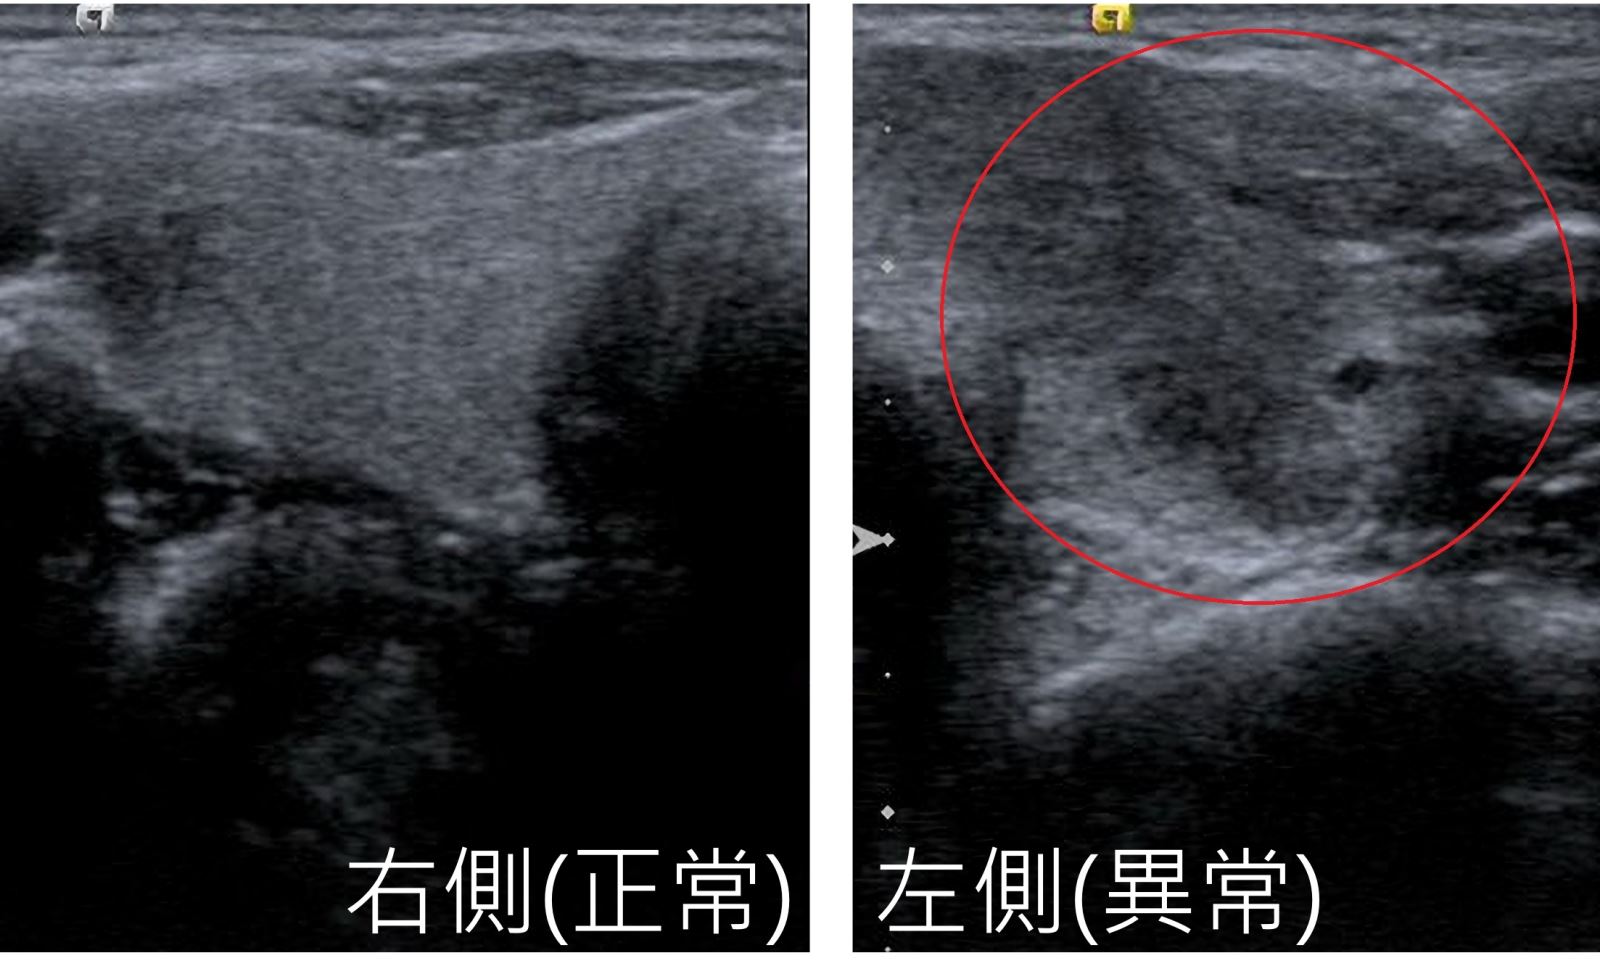

35歲王姓少婦因左側脖子腫脹(圖1)、劇烈疼痛,先至耳鼻喉科診所治療,服藥後疼痛稍微改善,幾天後又出現發燒及心悸,於是轉診至新陳代謝科門診,經過抽血及甲狀腺超音波檢查,診斷為亞急性甲狀腺炎,給予類固醇治療後,隔天脖子疼痛戲劇化好轉,和先前痛不欲生的模樣判若兩人。

當下先用手觸摸脖子,發現她的左側甲狀腺有硬的腫塊及明顯壓痛,安排抽血檢查,紅血球沉降指數(ESR)57(正常< 20)、甲狀腺功能TSH 0.016 (正常0.34-5.6)以及freeT4 2.6(正常0.54-1.4)異常,顯示有甲狀腺毒血症,於是再安排甲狀腺超音波檢查,發現左側甲狀腺有一大片邊界不清楚且內部不均勻的低回音(圖2),確診為亞急性甲狀腺炎。